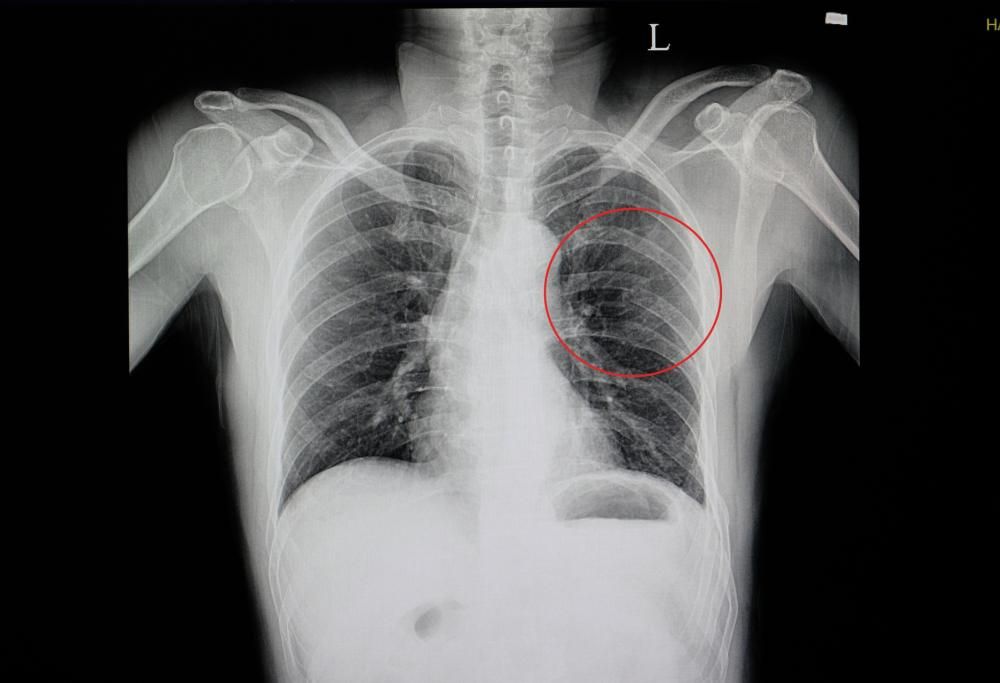

Una donna cinese di nome Huang ha avuto un grave incidente dopo aver mangiato troppo piccante. La donna ha avuto un attacco di tosse tale da rompersi ben 4 costole!

A onor del vero la donna era stata avvertita dai medici di essere eccessivamente fragile nella parte superiore del corpo e di dover fare molta attenzione. Huang è molto magra e la sua costituzione così esile (pesa appena 57 chili ed è alta 1,71 metri) la rende particolarmente debole. Dopo aver mangiato un cibo che è risultato essere fastidiosamente piccante per lei, la donna è stata presa da un micidiale attacco di tosse e mentre tossiva ha sentito un “crac”. La donna dopo quel momento aveva difficoltà a parlare, camminare e respirare, così si è rivolta a un medico. La TAC ha rivelato che c’erano 4 costole leggermente rotte. Il suo peso non aveva la forza muscolare per reggere la sua struttura ossea. La donna ha in effetti ammesso di non fare alcun tipo di attività fisica, quindi anche se il suo indice di massa corporea rientra nella normalità, rimane molto debole.